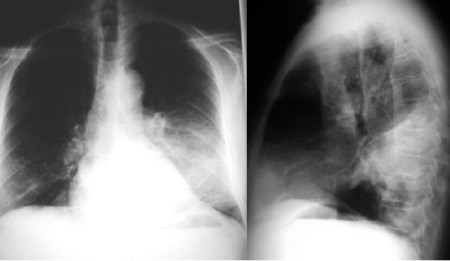

SIGNO DE LAS ALAS DE MARIPOSA INVERTIDAS

La presencia de infiltrados alveolares de disposición periférica y bilateral, respetando las regiones perihiliares, provoca una imagen opuesta a la del signo de las alas de mariposa. Este hallazgo se ve en la neumonía eosinófica.

La imagen de la TC muestra los focos de condensación alveolar periféricos y bilaterales, con predominio en el pulmón derecho.